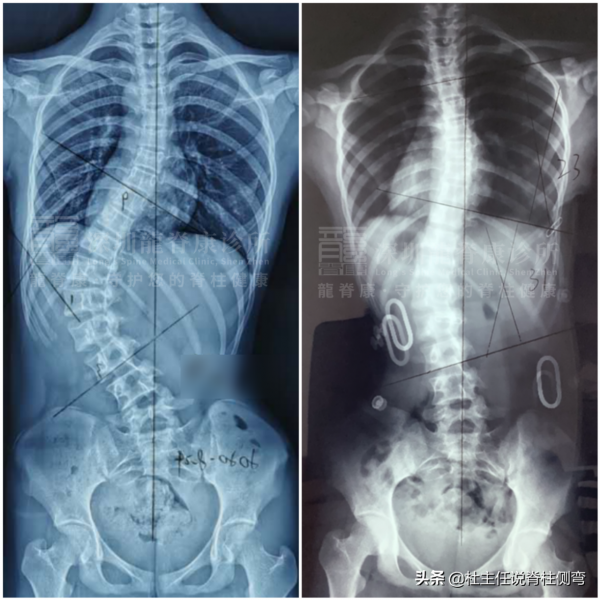

不僅如此,除了上述說到的表現之外,患有小胖威利兒童中脊柱側彎的發生率在40–90%,通常在兩個年齡段出現脊柱側彎發病高峰。

因此在生長激素治療前和治療後,每6-12個月進行全脊柱X線片檢查,以診斷小胖威利患者脊柱側彎型別,確定是否需要矯形治療。